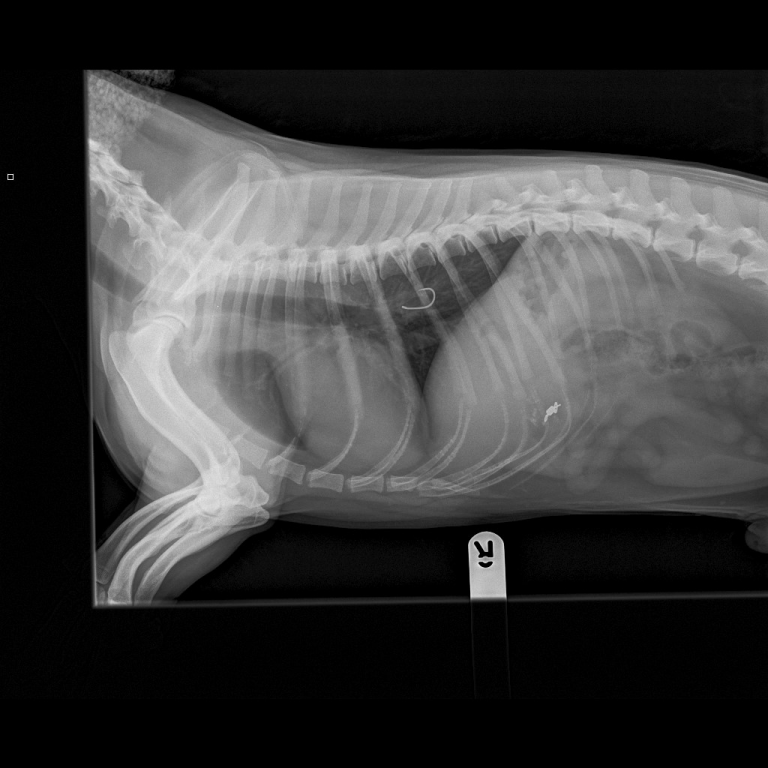

Curiosity almost killed the cat when a precious family pet nearly died after swallowing a toy doll’s plastic shoe.